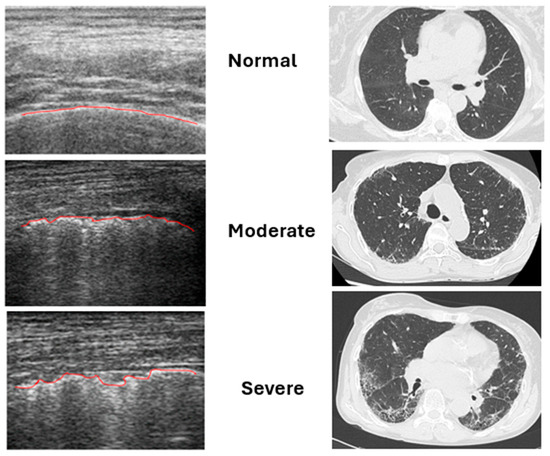

The Role of Ultrasound Pleural Irregularities in the Identification of Interstitial Lung Disease in Idiopathic Inflammatory Myopathies

Background: Interstitial lung disease (ILD) is the most frequent extra-muscular manifestation in patients with idiopathic inflammatory myopathies (IIMs). Although high-resolution chest tomography (HRCT) represents the gold standard for the evaluation of ILD, lung ultrasound (LUS) might be a useful tool for its [...] Read more.

Background: Interstitial lung disease (ILD) is the most frequent extra-muscular manifestation in patients with idiopathic inflammatory myopathies (IIMs). Although high-resolution chest tomography (HRCT) represents the gold standard for the evaluation of ILD, lung ultrasound (LUS) might be a useful tool for its assessment. The aim of our study was to evaluate the number and distribution of pleural irregularities (PIs) identified by lung US in a cohort of patients with IIMs and to find possible correlations with clinical, serological and HRCT data to verify the potential usefulness of lung US for the study of ILD in patients with IIM. Patients and methods: Fifty-three patients with IIM according to EULAR/ACR classification criteria were enrolled. All patients underwent a clinical evaluation with measurement of disease activity and myositis-specific autoantibodies, pulmonary function tests, HRCT evaluated with the Warrick score, and lung US for the measurement of PIs. Results: The number of PIs was higher in patients with myositis-specific autoantibodies, particularly those with anti-synthetase autoantibodies (p < 0.001) and in patients with high-grade dyspnea (p < 0.03). A negative correlation was identified between PIs and pulmonary function tests, particularly TLC (r = −0.74; p < 0.001) and DLCO (r = −0.56; p < 0.001). Interestingly, PI score was higher in patients with ILD identified with HRCT (p = 0.015) and a positive correlation between PIs and Warrick score (r = 0.542; p < 0.001) was also found. Conclusions: The study of PIs with lung US represents a promising diagnostic tool for the bedside evaluation of patients with IIMs. This can possibly allow for a reduction in unnecessary HRCTs, reducing the exposition of patients to ionizing radiations, optimizing resources and reducing the costs of patients’ management. Full article